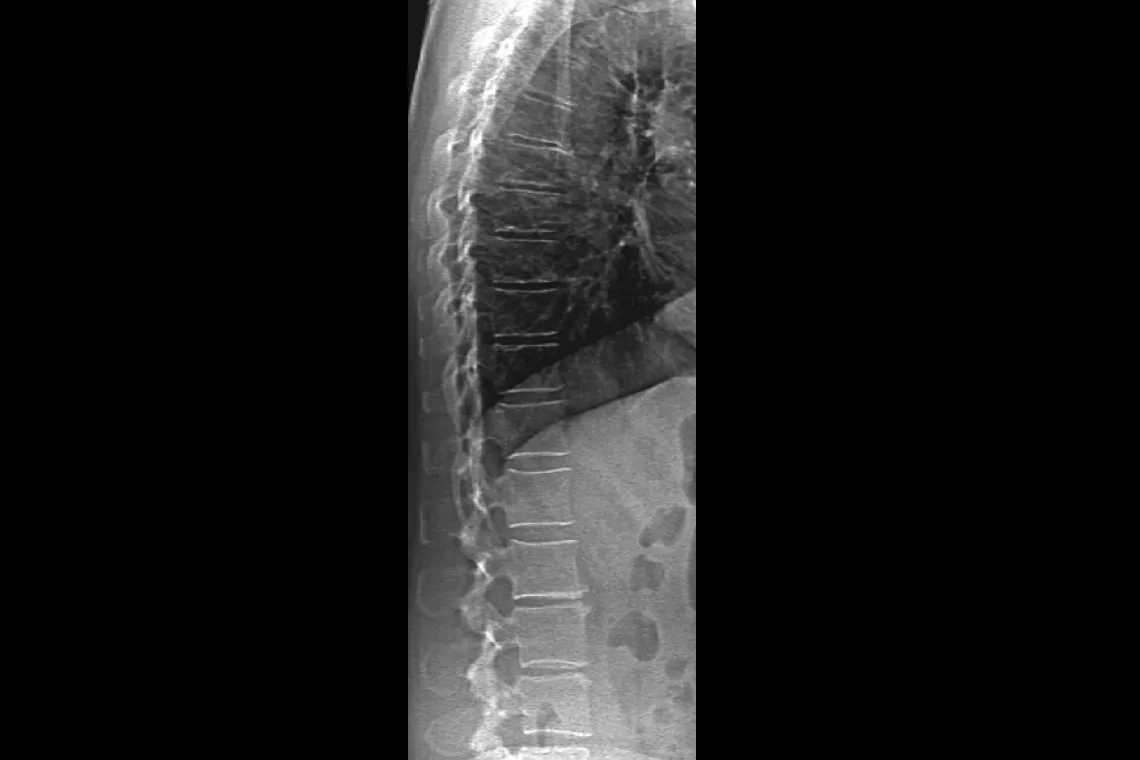

Assess fracture risk by combining an accurate measurement of bone density with high-resolution vertebral imaging. You can identify spine fractures with a low-dose, single-energy image in 10 seconds.

Improve accuracy and reduce post-exam analysis errors with precise, software-assisted placement of inter-vertebral disc spaces for graphic analysis.